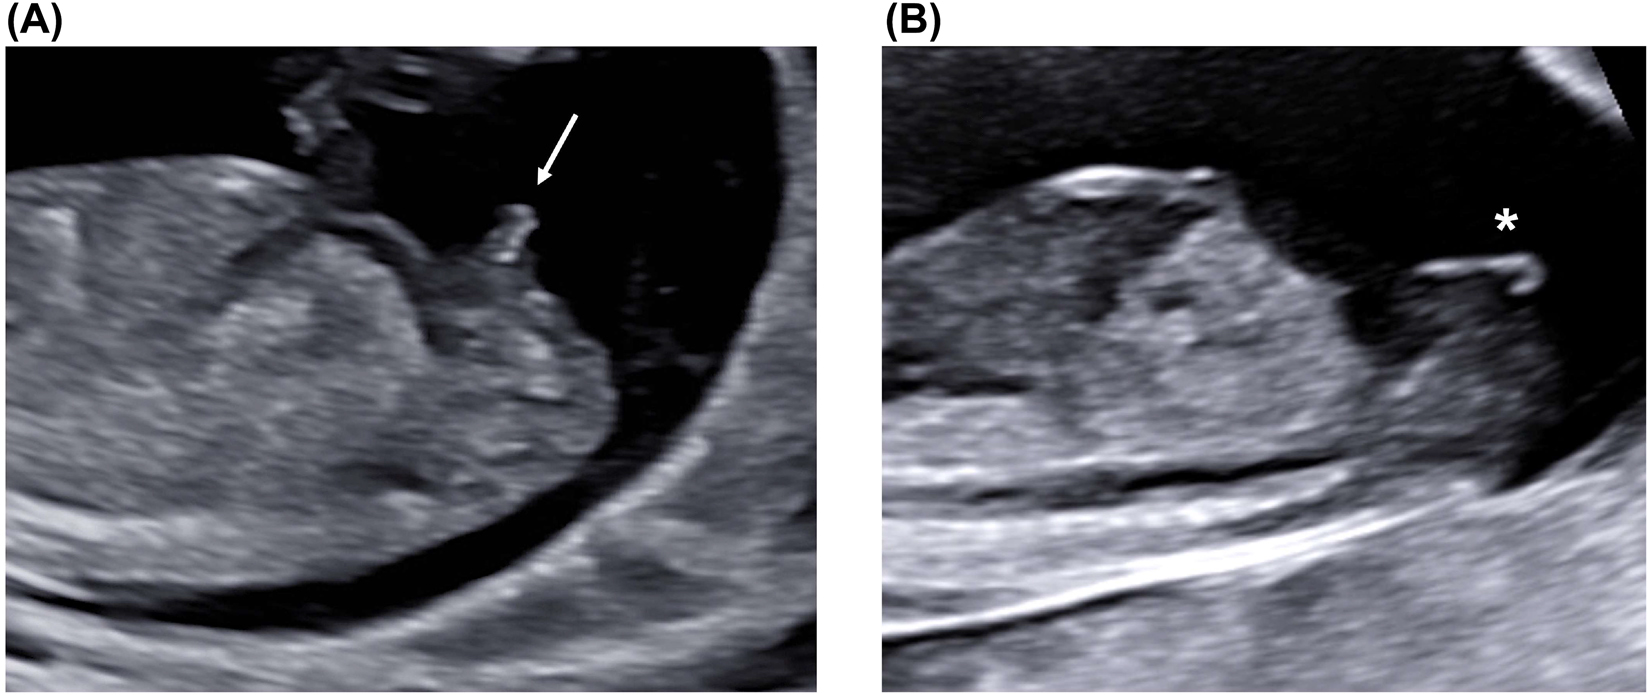

Face

The fetal profile is usually visualized on the midsagittal view of the fetus, showing fetal forehead, nose, lips, and chin (Figure 2). The profile should neither be flat nor show any protruding structures. The nasal bone should be visible and brighter than the overlying skin. Two anechoic orbits are usually visible on axial view, similar in size, with an oval lens within each orbit, close to its anterior surface (Figure 4). Fetal bony palate and upper lip could also be evaluated, showing no clefts or disruptions (Figure 5).

Fetal eyes and lenses on an axial plane (arrows).

Fetal bony palate (arrows) on coronal (A) and axial (B) planes.

The bony palate represents the base of the retronasal triangle visible on the coronal plane (A, arrow), whereas the alveolar ridge (arrows) and upper lip (*) are visualized on the axial plane (B).

The evaluation of fetal eye orbits and bony palate are not recommended on a routine basis but suggested during the first trimester fetal anatomic survey.